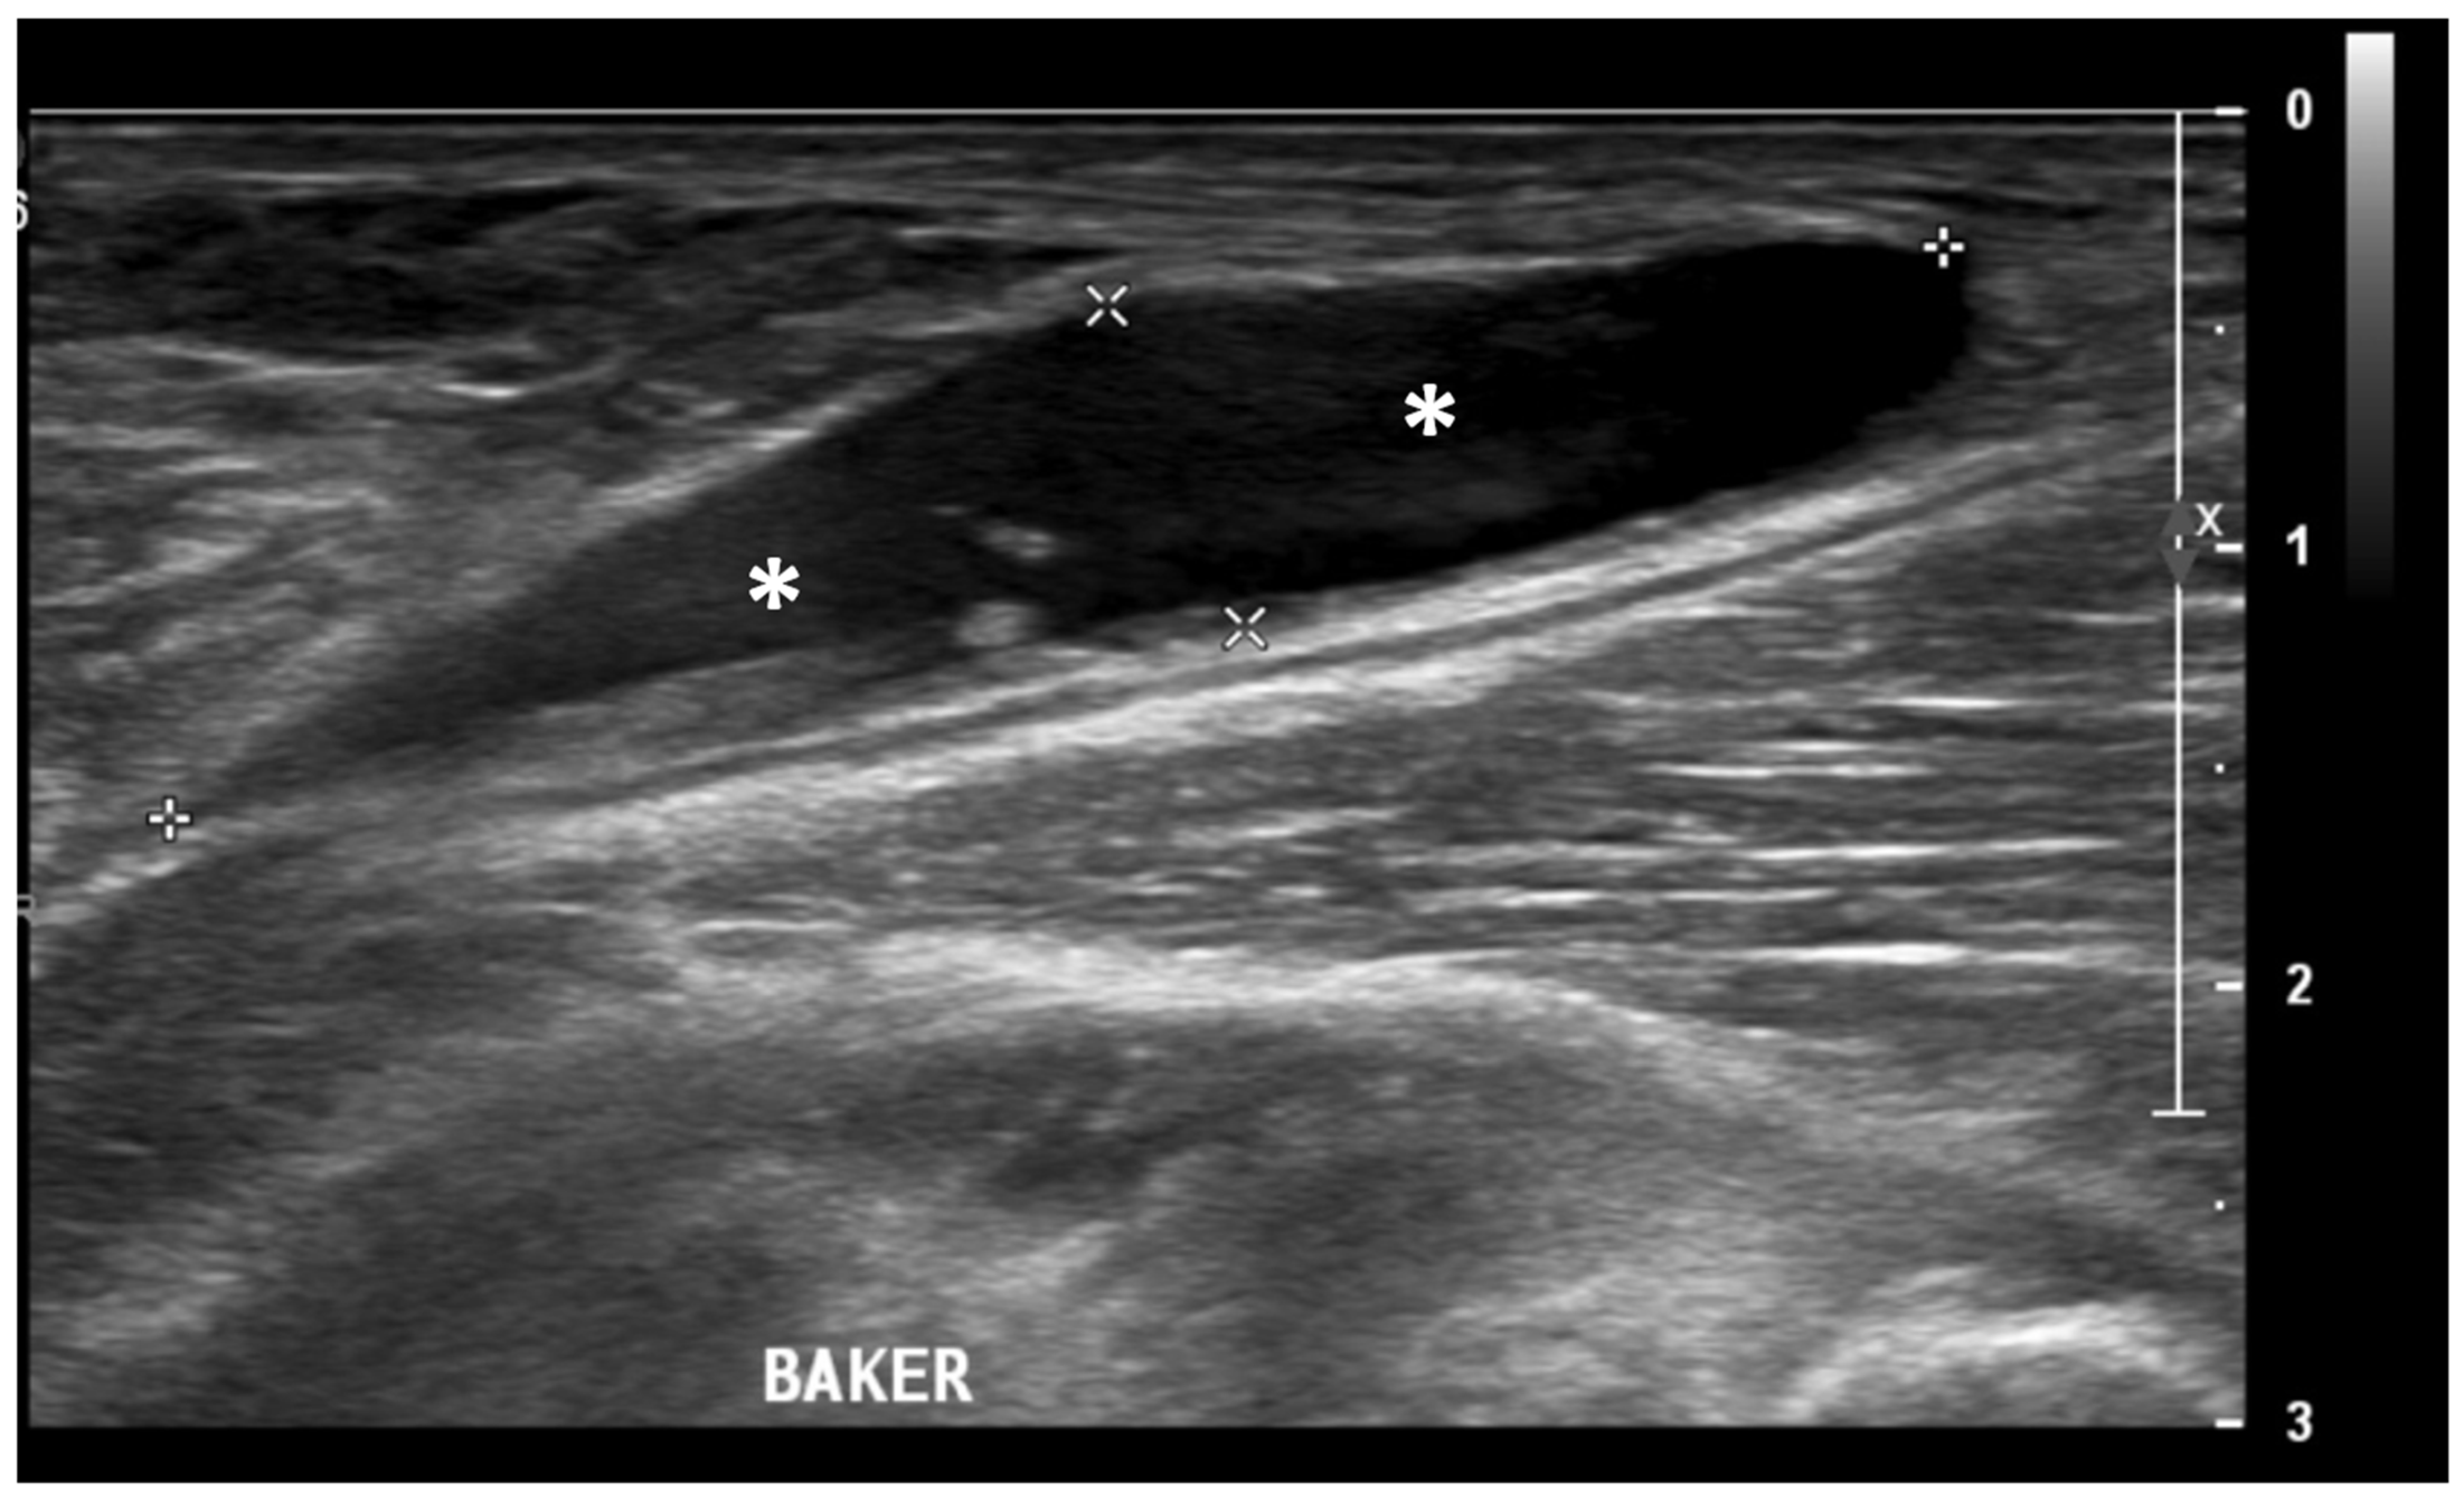

Ultrasound (US) imaging has not traditionally been used as part of the clinical pipeline for OA diagnostics. However, when examining the scientific literature, its role has risen steadily during the last two decades. US assessment of joints offers several advantages, including the ability to assess soft-tissue changes associated with OA and to outline the contour of the bony surface surrounding the joint [64,65]. In addition to detecting structural OA changes, a US can provide insights into inflammatory findings, complementing traditional CR imaging [66]. Several inflammatory findings (e.g., joint effusion/Baker cyst, synovial thickening, and hyper-vascularity), easily detectable throughout a US, are associated with pain exacerbation and disease progression in knee OA (Figure 2, Figure 3 and Figure 4).

Figure 4.

Ultrasound image (B-mode) longitudinal posterior view in the medial aspect of the popliteal fossa showing large fluid collection (asterisks) within the medial head of the gastrocnemius and the semimembranosus tendons’ sheet (Baker’s cyst).